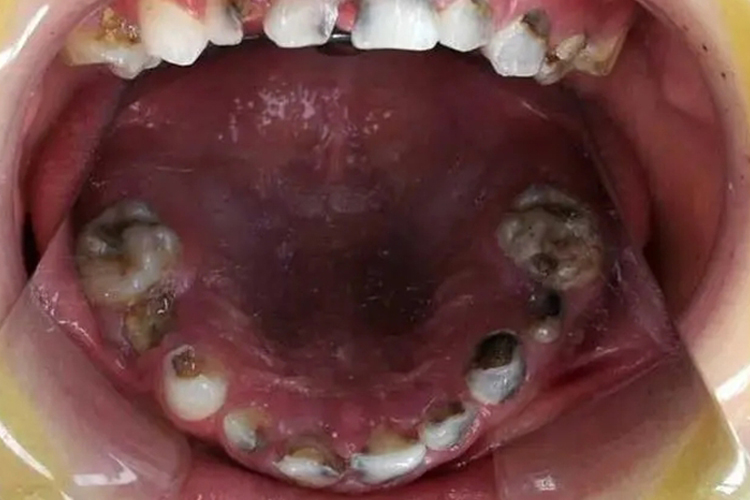

小孩不刷牙牙齿坏掉,多是发生了龋齿,龋齿根据累及的层次可分为浅龋、中龋、深龋,龋坏程度不同,症状表现不同。

浅龋:此时龋坏只在牙釉质层,牙齿表面可出现黑色、白色或黄色斑点,一般无明显龋洞,无自觉症状。

中龋:此时病变达到牙本质浅层,龋损部位牙本质呈黄褐色或深褐色,可在牙齿表面形成龋洞,并且对冷、热、酸等刺激较为敏感,刺激去除后症状立即消失。

深龋:此时病变已达到牙本质深层,在牙齿表面可出现深龋洞,并且可出现持续性疼痛或自发性阵痛。